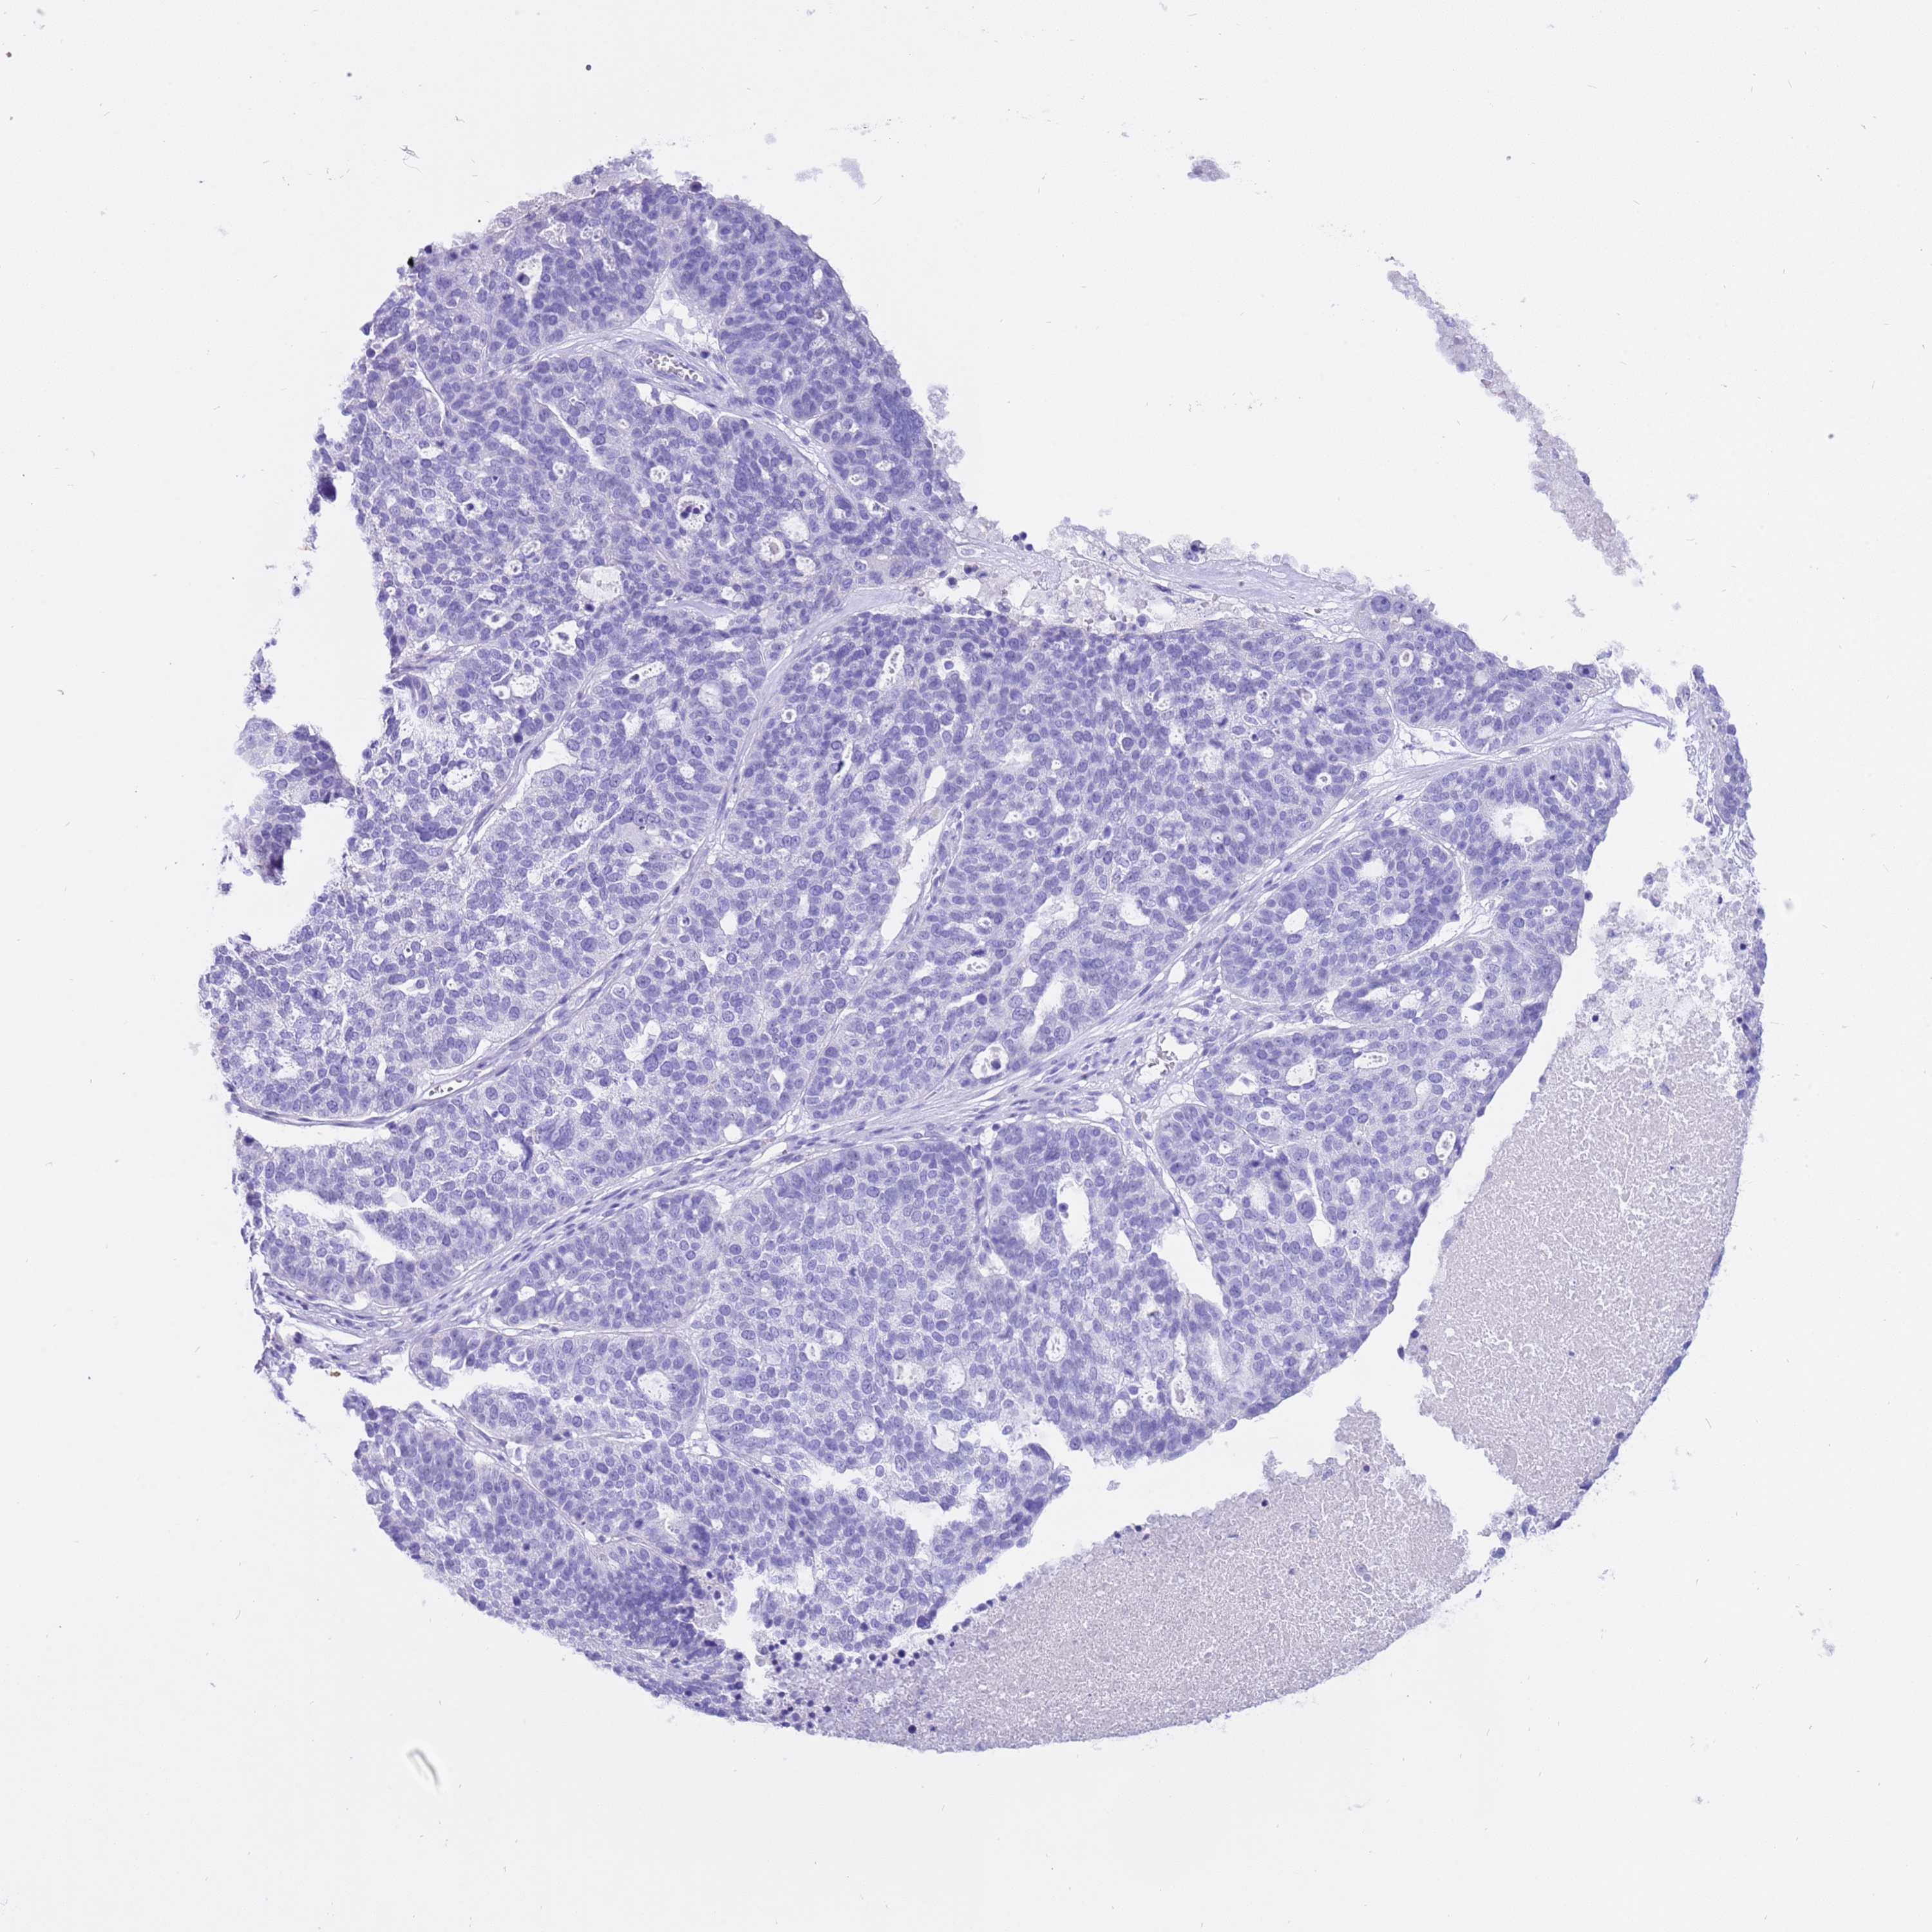

OVARIAN CANCER - Protein expressioni

A mouse-over function shows sample information and annotation data. Click on an image to view it in a full screen mode. Samples can be filtered based on level of antibody staining by selecting one or several of the following categories: high, medium, low and not detected. The assay and annotation is described here.

Note that samples used for immunohistochemistry by the Human Protein Atlas do not correspond to samples in the TCGA dataset.

Antibody stainingi

Antibody staining in the annotated cell types in the current human tissue is reported as not detected, low, medium, or high, based on conventional immunohistochemistry profiling in selected tissues. This score is based on the combination of the staining intensity and fraction of stained cells.

Each image is clickable and will lead to virtual microscopy that enables deeper exploration of all samples and also displays staining intensity scores, fraction scores and subcellular localization as well as patient and tissue information for each sample.

Antibody HPA038069

Antibody HPA046340

Antibody CAB026158

Cystadenocarcinoma, serous, NOS

Carcinoma, endometroid

Cystadenocarcinoma, mucinous, NOS

Carcinoma, NOS